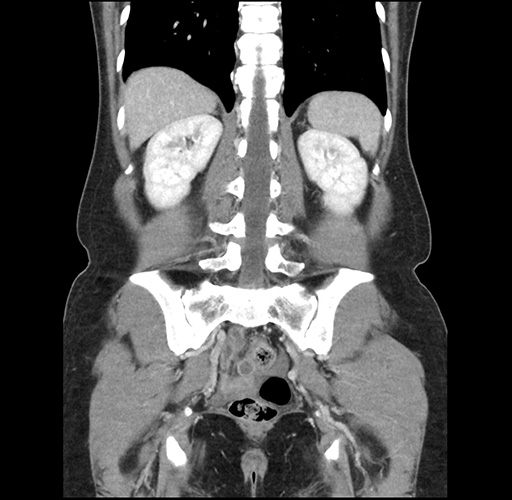

Imaging Analysis

Look through the patient's CT scan to identify any areas of concern for the necessary procedure.

Based on your CT findings, which issue(s) would give reason for "planned slowing down moment(s)" in this case?

Considering a standard left lateral sectionectomy procedure, what step(s) of the operation would you do differently in this case ?